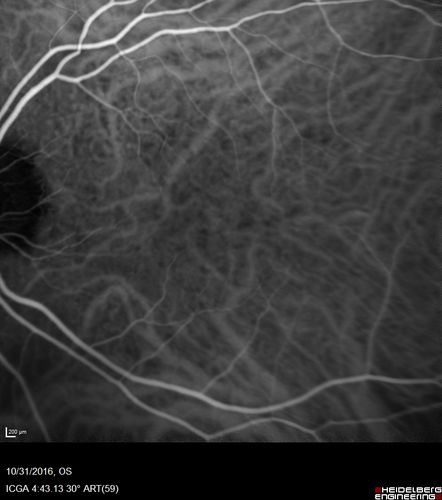

Submacular Hemorrhage - wet AMD

84 year old man with 20/200 from submacular hemorrhage. Vision improved to 20/32 with only Avastin therapy (no surgical intervention). The initial FAF is interesting because parts of the blood hyper auto fluoresce.